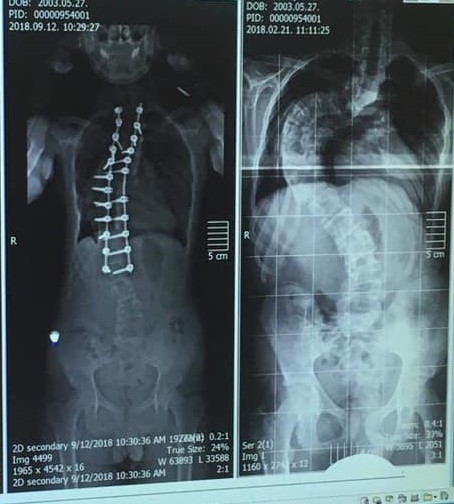

Az Aranyanyu-díjas Schuster Barbara egy azon nők közül, aki komoly betegséggel küzdött, majd egy sikeres gerincműtét jelentett számára gyógyulást. Az évekig tartó orvosi vizsgálatok, specialisták felkutatása és konzultációk sora után végül felnőtt korában valósulhatott meg az operáció, amely komoly elhatározást ébresztett benne: eldöntötte, hogy gerincferdüléses betegek támogatásával szeretne foglalkozni. Jelenleg a Vertebra Alapítvány koordinátoraként több száz fős közösség életét szervezi, feladatai közül egyik legfontosabbként említi a műtét előtt álló gyerekekkel és szüleikkel való tájékoztató, felkészítő beszélgetéseket.

Én is tinédzserkorban vettem észre, akkor lett feltűnő, az esetek legnagyobb hányadában így van. Ma már tudjuk, hogy az én betegségem egy veleszületett fejlődési rendellenesség volt, tehát jelen volt születésemtől fogva, de igazából kamasz koromban lett látványos. Az én gerincferdülésem a ritkább típusba tartozott, de a gerincferdülések nagy hányadát kitevő ún. ismeretlen eredetű típus is jobbára a tinédzser hormonális változásával egyidőben „robban be”, akkor tud nagyot romlani.

Egész gyerekkoromban tehetetlenül álltak az esetem felett az orvosok. Fiatal felnőttként indultam újra megoldást keresni, de megint csak egyre elkeserítőbb szakvéleményeket kaptam. Volt olyan sebész, aki azt állította, hogy biztosan megbénulok műtéttel vagy anélkül is. Nagyon nehéz időszak volt, reménytelennek láttam a helyzetem. A családom segítségével kerültem egy Svájcban dolgozó magyar gerincsebészhez. Akkor már nagyon fáradt voltam, nem is akartam elmenni a vizsgálatra, mert úgy éreztem, nincs szükségem a következő lemondó sóhajra. Végül ott, ezen a vizsgálaton fordult meg a történetem, az egész életem, hiszen ez az orvos a maga nagyon szerény módján közölte velem, hogy ezt ő meg tudja gyógyítani. Igaza lett: fél évvel később, huszonöt éves koromban operált meg Svájcban, a műtét bravúrosan sikerült. Mindent álmom valóra vált: az S-alakú gerincem egyenes lett, a bordadeformitásom eltűnt. Katartikus gyógyulást jelentett ez számomra, hiszen akkor már legalább 10 éve vártam erre a pillanatra.

Tudni kell, hogy ez a legnagyobb orvosi beavatkozások egyike, amit gyerekeken végeznek. 6-8, de akár 10-14 órás lehet egy ilyen műtét, ez már eleve rengeteg félelmet ébreszt mindenkiben. Kockázatos műtét, a legnagyobb veszélye a bénulás. Azonban – és ezt büszkén, örömmel mondom – Magyarországon három klinikán elérhető ez a műtéti eljárás, nagyon magas szakmai színvonalon és nagyon felkészült szakemberek várják a pácienseket.

Már utaltam rá, hogy a gerincferdülésnek két nagy csoportja van, az úgynevezett idiopathiás vagy ismeretlen eredetű gerincferdülés, és a másik csoport, amikor ismert a gerincferdülés kiváltó oka - például fejlődési rendellenesség, valamilyen alapbetegség, szindróma. Az ismeretlen eredetűből jóval több eset van, több ezer gyereket érint. Őket kezelik fűzővel. Nehéz ügy ez, a fűző és a gyógytorna, mert egyik sem garantálja száz százalékig, hogy a gerincferdülés romlását meg lehet állítani. Ennek tudatában kell egy gyerekkel következetesen betartatni a kezelést, ami lássuk be, nagyon nem könnyű. A másik jellemző probléma, hogy még mindig nagyon sok a tévhit és félrekezelés ezen a területen. Két jellemző mondat él még mindig sajnos a gerincferdüléssel kapcsolatban: „ússzon a gyerek” vagy „majd kinövi”. A tévhitek nagyon emelik a látenciát, hiszen nem megfelelő időben vagy nem jó kezelést kapnak miatta a gyerekek. El kell felejteni, hogy a nehéz, egyoldali iskolatáska, az egykezes sportok, a rossz tartás, az SMS-ezés okozhat ilyet. A kérdésre visszatérve, a fűző és a gyógytorna komoly esély a gerincferdülés romlásának megakadályozására, de nem minden esetben jelent segítséget. Statisztikát nem tudok mondani, de rendkívül sok gyermeket, fiatalt és felnőttet érint a gerinckorrekciós műtét, amely Magyarországon három klinikán is elérhető magas szakmai színvonalon. A gerincferdülés másik típusában igen jellemző a műtéti kezelés szükségessége.